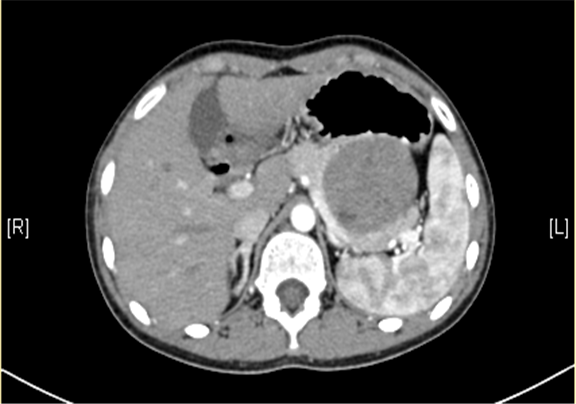

上腹部三维CT动态增强扫描: 胰腺体尾部类圆形软组织肿块,考虑实性假乳头状瘤可能性大。

术前CT检查:

静脉期